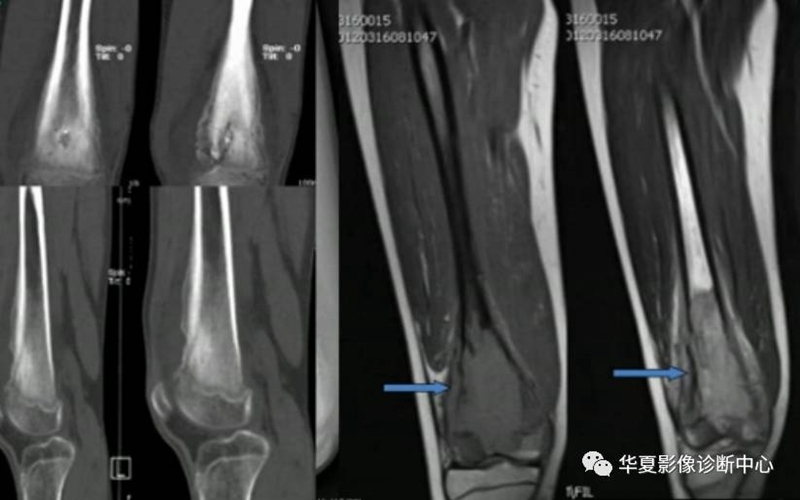

首先是肿瘤与感染鉴别,可从病史,骨质破坏与骨质增生、病变范围,骨膜增生、软组织的改变等方面进行鉴别。

左为亚急性化脓性骨髓炎,右为骨肉瘤